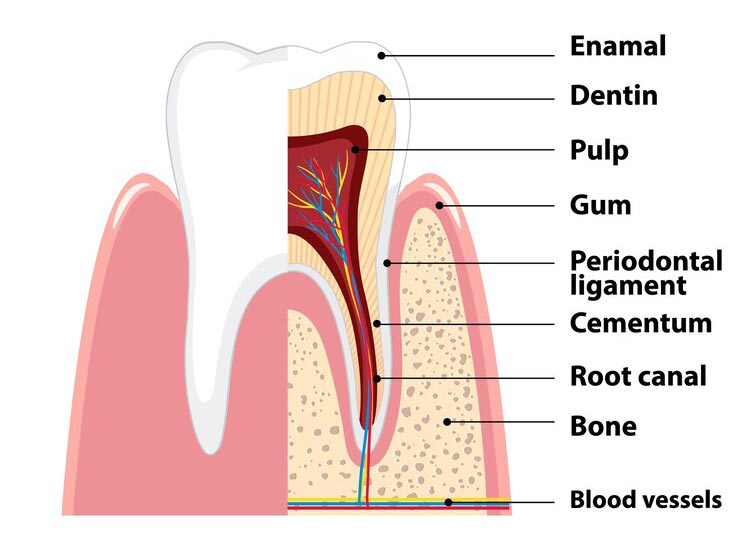

درمان ریشه دندان به معنای خارج کردن عصب یک دندان، تمیز کردن و شکل دادن به فضای کانال است و در آخر نیز جهت ممانعت از ورود میکروب و باکتری به عصب دندان باید دندان را پر کنند. درمان ریشه دندان به این جهت انجام می شود که دندان را هر چند بدون عصب زنده داخل دهان داشته باشیم و در کنار آن نیز در زمان خوردن درد نداشته باشیم. دندانپزشک متخصص در کلینیک دندانپزشکی تریدنتال می تواند بهترین خدمات را در این زمینه به شما ارائه دهد. همچنین باقی ماندن دندان داخل دهان باعث حفظ زیبایی و ظاهر بیمار نیز می گردد. درمان ریشه دندان معمولاً نیازمند یک یا دو جلسه ملاقات با پزشک می باشد، اما در بعضی موارد ممکن است به علت سختی کار یک جلسه دیگر نیز به دوره درمان ریشه دندان اضافه شود.

در این روش پس از حذف پالپ ناحیه تاجی و ریشه ای، به منظور کامل کردن فرایند درمان ریشه دندان، چند اقدام دیگر را انجام می دهد. وی با استفاده از وسایل تخصصی ویژه، فرایند تمیز کردن و عاری کردن داخل کانال های ریشه دندان از محتویات را انجام داده به نحوی که در پایان این مرحله اطمینان می یابد که کانال عصبی کاملا تمیز و عاری از هر گونه آلودگی است. وی برای انجام این کار بارها پس از عمل ساییدن دیواره های کانال، با کمک سرم فیزیولوژی اقدام به شستشو مکرر نموده و قطعات جدا شده حین عمل سایش را خارج می نماید.

تفاوت درمان ریشه دندان و عصب کشی

در این روش درمانی متخصص معالجه ریشه دندان، فقط بخش آلوده پالپ دندان را حذف نموده و سپس با کمک مواد زیست سازگار ویژه ای سعی می کند که ضمن ترمیم ناحیه صدمه دیده، الباقی پالپ دندان را حفظ کرده و نجات دهد. در واقع در پایان این درمان، ضمن آن که بیمار وارد فاز عصب کشی نشده و دندانش همچنان دارای عصب و خون می باشد و حیات دارد، روند عمر طبیعی دندان نیز ادامه یافته و دندان در مقابل تحریکات طبیعی پاسخی مناسب می دهد.